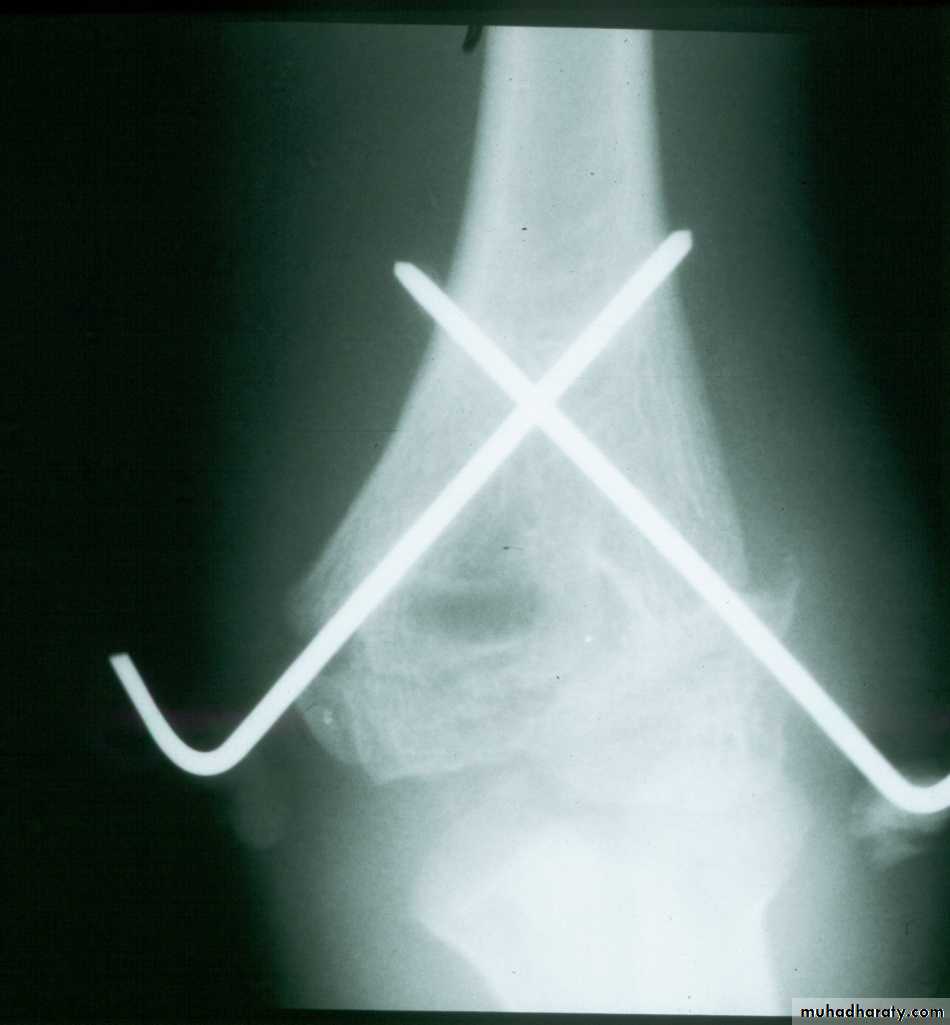

Percutaneous

pin

fixation

If a cast is inadequate,

then what is the standard for maintaining the reduction?

Medial-lateral

pins

In what manner may the pins be used?